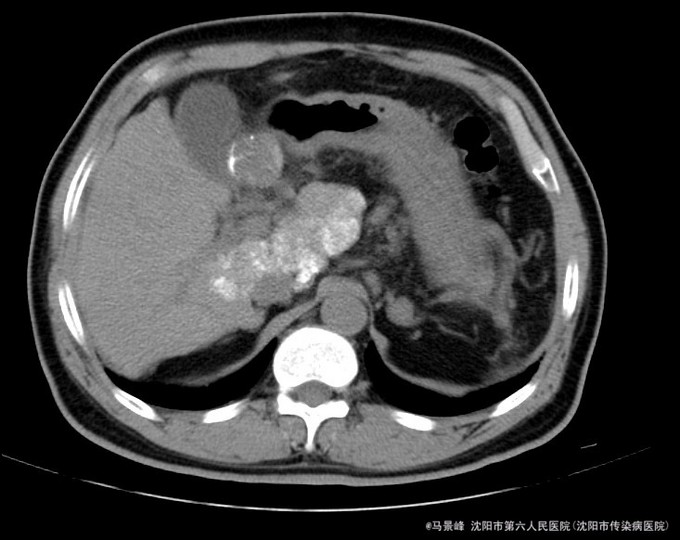

查体:巩膜无黄染,心肺听诊无异常,腹软,无压痛,肝脾肋下未触及,移动性浊音阴性,双下肢无浮肿。 入院后化验结果:丙氨酸氨基转移酶 24 U/L、天门冬氨酸氨基转移酶 36 U/L、碱性磷酸酶 101 U/L、γ-谷氨酰转肽酶 96 U/L、胆碱酯酶 6127 U/L、总蛋白 80.8 g/L、白蛋白 41.4 g/L、总胆红素 30.0 umol/L、结合胆红素 0.0 umol/L、非结合胆红素 16.5 umol/L、δ胆红素 13.5 umol/L。葡萄糖 7.77 mmol/L。乙型肝炎病毒表面抗原 阳性(+) 、乙型肝炎病毒核心抗体 阳性(+) 。甲胎蛋白 3.49 ng/mL。 CT检查示:肝脏形态不规整,肝裂增宽,肝尾叶体积相对增大,各叶大小比例失调,肝实质密度不均,肝内可见多个大小不等结节影,较大者位于肝Ⅳ段胆囊旁,其边缘可见条状碘油沉积,大小约3.3x3.05cm,增强扫描动脉期其边缘轻度强化,门脉期及延迟期扫描呈稍低密度,病灶内坏死区未见强化,其余结节无明显强化,较大者位于Ⅷ段,约1.2cm大小,延迟期呈稍低密度,门脉主干及左右支纤细,左支充盈欠佳,脾脏缺如,胆囊不大,壁增厚,其内密度均匀,胰头区可见一囊性密度影,大小约2.11cm,增强扫描无强化。肝内外胆管未见明显扩张,食管下段胃底贲门区见扩张扭曲的血管影,腹膜后未见明显肿大淋巴结。 患者CT所见胆囊旁病灶碘油流失,且动脉期仍有强化,提示肿瘤仍有血供。

诊断:1、乙肝肝硬化 失代偿期;2、原发性肝癌TACE术后 治疗:入院后除加强休息、抗病毒治疗外,行增强CT检查,发现肝癌TACE治疗后胆囊旁病灶碘油流失,且动脉期仍有强化,提示肿瘤仍有血供。遂于局麻下再次行TACE治疗。